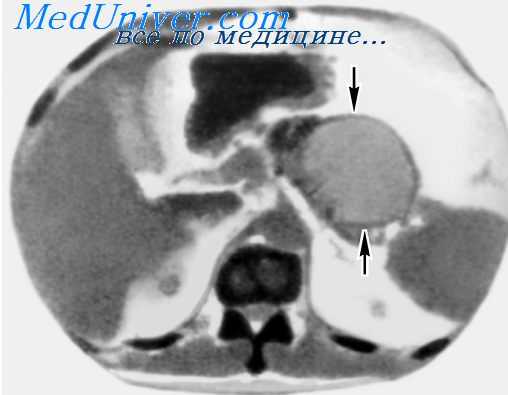

3. Компьютерная топография более чувствительна по сравнению с УЗИ. КТ позволяет проводить дифференциальную диагностику псевдокист. Кроме этого возможна пункция и дренирование псевдокист под контролем КТ.

КТ органов брюшной полости. Псевдокиста поджелудочной железы у пациента после приступа острого панкреатита